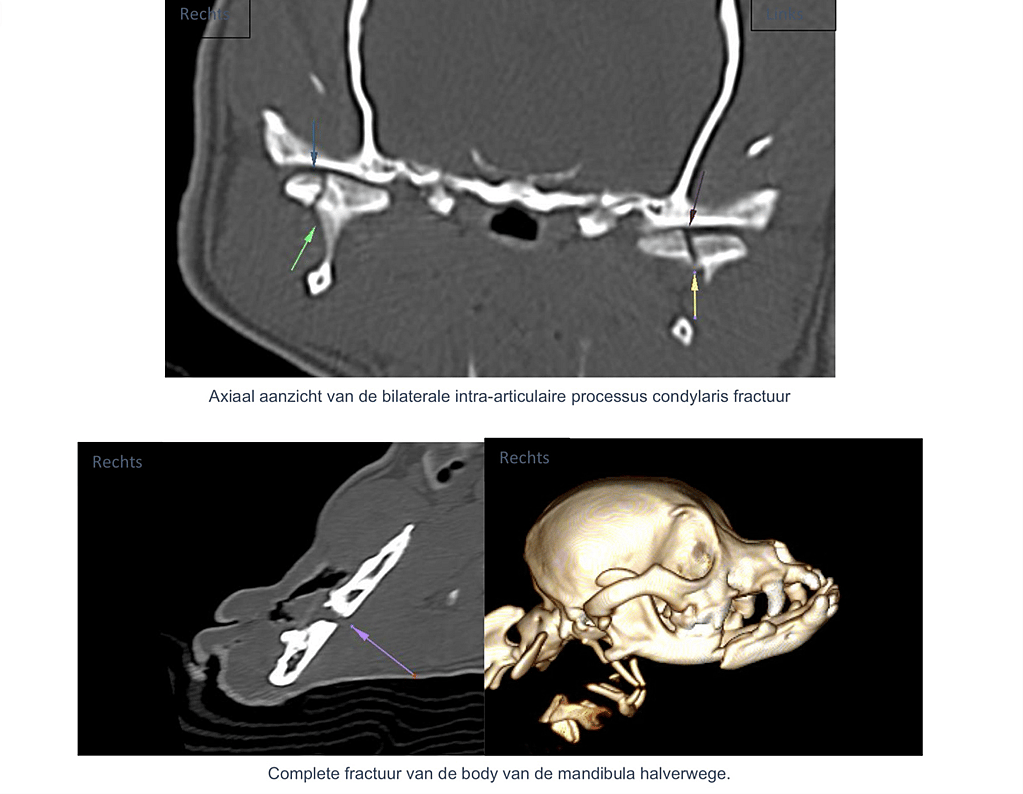

Axiale en sagittale CT-beelden tonen een complete fractuur halverwege de corpus mandibula, met lichte rotatie van het caudale fragment.

Verschuiving is goed zichtbaar op de 3D-reconstructie. - Linker processus coronoideus – complete overlangse fractuur

Op coronale CT-beelden zijn bilaterale fracturen van het laterale condylaire aspect zichtbaar, zonder verplaatsing.

De TM-gewrichten blijven morfologisch en positioneel congruent.